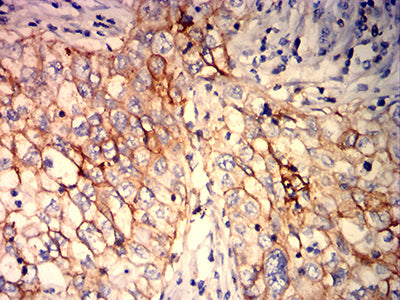

分类: 科研抗体货号: 32257别名: hK2; hGK-1; KLK2A2应用: IHC,FCM反应种属: Human

分类: 科研抗体货号: 32255别名: HO-1; HSP32; HMOX1D; bK286B10应用: IHC,FCM反应种属: Human

分类: 科研抗体货号: 32254别名: HO-1; HSP32; HMOX1D; bK286B10应用: IHC,FCM反应种属: Human